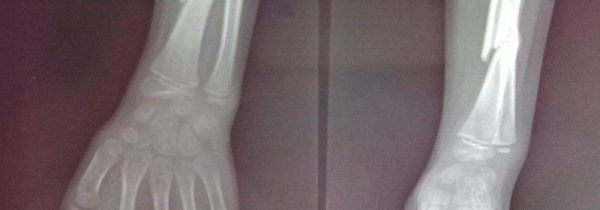

尺骨和桡骨的位置

尺骨的位置在胳膊内侧,前臂两根长骨之一中较长的骨头就是尺骨,围殴哦小手指的一侧。尺骨分为上端、下端、体三部分,上端较为粗大,前面有一个半月形的关节面,叫做半月切迹,而尺骨前下方凸起的叫冠突。

桡骨的位置在上肢前臂,手臂下垂手心向前对立时,靠外侧的就是桡骨,也就是靠近大拇指一侧的为桡骨。桡骨的上端是扁圆形的头,而头的上面有凹陷的桡骨头凹。下端较为粗大,参与挠骨关节的组成。

尺骨和桡骨都是人体上肢前臂的骨头之一,并且都是长骨头。从两者的位置关系来看,尺骨在前臂的内侧,而桡骨位于前臂的外侧,在医学里面也有一个标准的说法来形容它们的位置关系,就是内尺外桡。